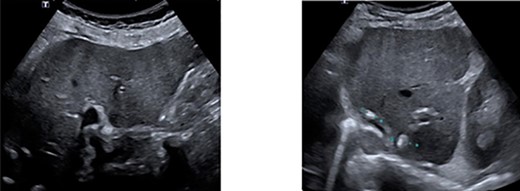

As part of follow-up 6 months after resection, laboratory tests for CEA, an ultrasound of the liver and a colonoscopy were performed. Postoperative CEA was 4.0 ng/mL. Ultrasound of the liver showed post-therapeutic changes after RFA and surgery. No metastases were found (Fig. 3). With colonoscopy, one polyp was found in the caecum. A punch biopsy was performed and revealed an adenoma with low-grade dysplasia.

Ultrasonography of the liver showing no progression of disease. A. Right lobe. B. Left lobe.